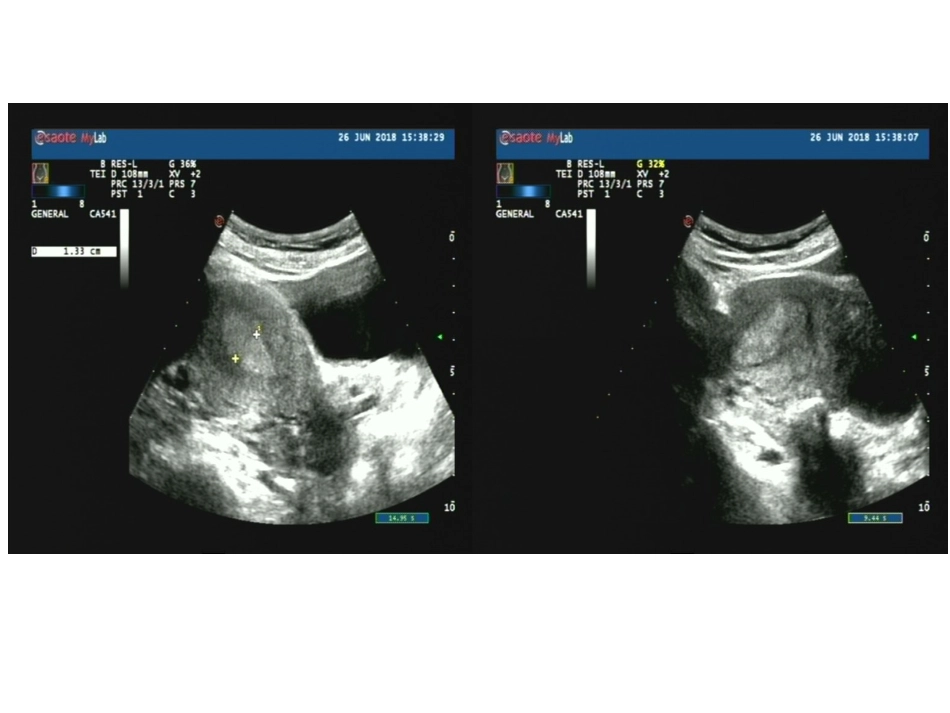

病例讨论南阳市第二人民医院超声科2018.7.10病史患者女36Y,3月前无明显诱因出现腹胀,自觉腹部增大,伴腹坠,有时尿不尽,无尿频、尿急、尿痛,无腹痛、发热、恶心、呕吐等不适,未检查及治疗。4天前于当地医院B超检查提示右侧附件区无回声区,现要求手术治疗入院,门诊拟以“盆腔包块”为诊断收住我科。近来,饮食、睡眠可,大小便正常,体重无明显改变。超声所见:子宫体积为55mm×46mm×50mm,形态正常,宫壁平滑,肌层回声均匀,内膜线居中,厚约13mm,宫腔内未探及异常回声。宫颈厚29mm,内可探及多个无回声区,较大一个为9mmx7mm。右侧卵巢可显示,右侧附件区未见明显包块声像。左侧卵巢显示不清,子宫左上方可探及153mmx84mm无回声区,边界清,上缘达脐上,内透声差,可见大量点状回声,其内左下方可见范围63mmx36mm低回声突起,边缘光整,CDFI:低回声周边可见血流信号。无回声内并可见大小21mmx17mm的囊性结构突起及16mmx9mm的混合回声突起。超声提示:盆腔囊实性包块,性质待定,不除外囊腺瘤可能宫颈潴留囊肿病理描述:盆腔包块:送检:7x6.5x3cm碎囊壁组织一堆,囊壁光滑,内附咖啡色样物,壁厚0.1-0.2cm。(取3盒);病理报告:(盆腔)符合巧克力囊肿。;(盆腔)符合巧克力囊肿。卵巢巧克力囊肿(chocolatecystofovary)又名卵巢子宫内膜异位囊肿,是子宫内膜异位症的一种病变。正常情况下,子宫内膜生长在子宫腔内,受体内女性激素的影响,每月脱落一次,形成月经。如果月经期脱落的子宫内膜碎片随经血逆流经输卵管进入盆腔,种植在卵巢表面或盆腔其他部位,形成异位囊肿,这种异位的子宫内膜也受性激素的影响,随同月经周期反复脱落出血,如病变发生在卵巢上,每次月经期局部都有出血,使卵巢增大,形成内含陈旧性积血的囊肿,这种陈旧性血呈褐色,黏稠如糊状,似巧克力,故又称“巧克力囊肿”。这种囊肿可以逐渐增大,有时会在经期或经后发生破裂,但很少发生恶变。卵巢巧克力囊肿虽然是良性疾病,却有增生、浸润、转移及复发等恶性行为。此类卵巢囊肿是25~45岁的生育年龄妇女最常见的疾病之一,发病率为10%~15%。子宫内膜异位病灶会随时间增加而变大,渐渐侵蚀正常组织,造成卵巢组织不可逆的损害。严重者需要手术处理。影像学检查:阴道和腹部B型超声检查是最简便易行的诊断方法。是鉴别卵巢子宫内膜异位囊肿的重要手段,其诊断敏感性和特异性均在96%以上,但直径小于1cm不易测出。B型超声检查可确定卵巢子宫内膜异位囊肿的位置、大小、形状和囊内容物,囊内有无乳头,提示囊性还是实性,与周围脏器特别是与子宫的关系等。超声图像一般显示囊肿呈椭圆形、圆形,囊肿可为单房或多房,与周围组织特别是与子宫有粘连,囊肿壁较厚且粗糙,囊内有点状细小的絮状光点。囊肿大小可随月经周期出现一定的变化。由于囊肿的回声图像无特异性,不能单纯根据超声图像确诊。盆腔CT及MRI对盆腔内异症的诊断价值与B型超声相当,但费用较昂贵。MRI对卵巢内膜异位囊肿的诊断和评估有意义。(2)血清CA125测定中、重度内异症患者血清CA125值可能会升高,但一般均为轻度升高,多低于100IU/L。但CA125的特异性和敏感性均局限,且与多种疾病有交叉阳性反应,目前无任何一种肿瘤标记物为某一肿瘤专一独特所有,因此不能单独用做诊断或鉴别诊断。对于CA125值升高者,血清CA125水平可用于监测异位内膜病变活动情况,治疗有效时降低,复发时升高。治疗:可采用药物或(和)手术治疗(保守性或根治性)。迄今为止,除根治性手术外,尚无一种理想的根治方法。无论是药物治疗抑或保守性乎术均有相当高的复发率。因此,应根据患者年龄、症状、体征、病变范围以及对生育要求、患者的主观愿望等因素加以选择,强调个体化治疗。主张选对药物积极治疗并结合密切随访复查,注意卵巢囊肿的性质变化,再采取相应的对策。症状轻或无症状的轻微病变选用期待治疗;有生育要求的轻度患者明确诊断后先行药物治疗,病情重者行保留生育功能手术;年轻但无生育要求的重症患者可行保留卵巢功能手术,并辅以药物治疗;症状及病变均严重的无生育要求患者可行根治性手术。手术方式有开腹手术和经腹腔镜手术两种。...